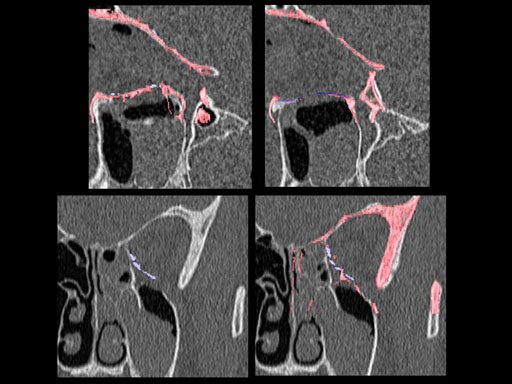

Furthermore, as orbital floor fractures are quite frequently associated with medial wall fractures; anatomic restoration especially in the transition zone between both wall is a demanding procedure. As described by B. Hammer, the orbital floor has an initial shallow convex section behind the rim, then inclines upward behind the globe, and inclines upward to meet the medial wall, creating a distinct bulge behind the globe. These convex curves of the medial wall and floor create a postbulbar constriction of the orbital cavity, which must be reconstructed when the orbit is rebuilt following fractures. Treatment is directed at precise anatomical reconstruction of orbital shape and volume in order to restore the correct position of the eye. To provide surgeons with an adequate implant that addresses the requirements of two wall acute orbital fractures or for secondary reconstruction of enophthalmos and dystopia, a new series of preformed orbital plates was developed for the new orbital matrix system.

Unlike the existing two-dimensional mesh implants, the geometry of the new preformed plates will be adequate to match the individual anatomic situation of the patient in almost any case. However, the mesh parts can be individually adjusted if necessary. In these cases the solid part in the central posterior area needs to remain untouched. Areas of the orbit that do not require a bridging can be spared out by trimming the implant along the designated cutting lines in the height of the medial wall and/or length of the orbital floor area. The lateral anterior part of the plate is intentionally pre-bent higher than the orbital rim anatomy to allow free plate movement during plate positioning.

The Preformed Orbital Plates are indicated for trauma repair and reconstruction of fractures of the orbital floor, medial orbital wall or combined fractures of floor and medial wall. It should be noted that in three-wall fractures where the lateral wall is also involved, a second orbital implant, ( i. e. the mesh plate) must be used in addition to the pre-formed orbital plate.

30 year old male patient with fracture of left orbital floor and medial wall.

Provided by Dr Dr Marc C Metzger, Freiburg, Germany.